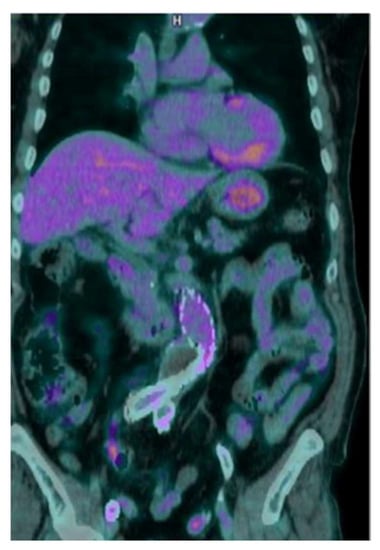

All PET/CT studies were correctly interpreted as negative by all the three readers, showing only mild and diffuse [18F]FDG uptake along the graft, without focal areas (Score 2) (Figure 4).

Figure 4.

Coronal view of a negative [18F]FDG PET/CT, showing mild and diffuse [18F]FDG uptake along the graft.